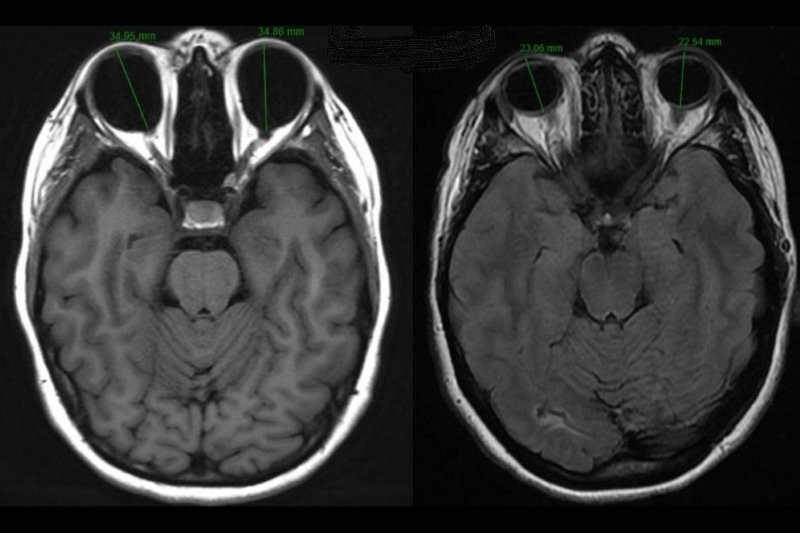

A 74-year-old fit and well Chinese man presented with a one-week history of right central blurring and visual acuity of 6/75. He was found to have submacular haemorrhage of around 6DDs with subretinal blood and coexisting pigment epithelial detachment confirmed on OCT (Fig 1).

Fig 1. Fundus image and OCT showing sub-macular

haemorrhage pigment epithelial detachment (PED)

At his most recent review, seven months after initial presentation, visual acuity was 6/9.5 (6/7.5 with pinhole), without any recurrence of nAMD activity eight weeks after injection. His PED had also reduced, with subtle pigmentary changes only (see Fig 3).

Fig. 3 Final follow-up of the patient

showing good macular architecture